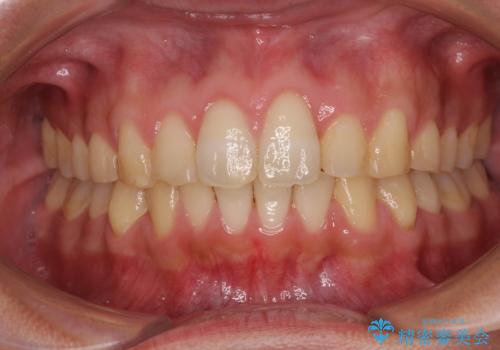

捻れて飛び出した前歯 インビザラインで整った前歯に

歯と歯の間を削ることでうまくスペースコントロールでき、また、毎日22時間以上しっかりとマウスピースを装着していただいたので、スムーズに治療が進みました。

治療途中で転勤となり、遠方からの通院となったため、来院間隔空いてしまいましたが、2年間で終えることができました。